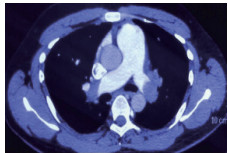

2 积极寻找补救性溶栓的治疗时机并非遥不可及例3 36岁,女性。主诉“活动后气短5 d、加重伴咯血1 d”。既往因月经不调,应用激素替代治疗20 d;否认手术、外伤及制动史。入院查体:神志清楚,体温36.8℃,血压110/75 mmHg,脉率118次/min,呼吸23次/min,脉氧饱和度90%(安静,空气氧),轻度乏氧征。双肺呼吸音清。心率118次/min,未闻及干、湿性啰音,心律齐,P2 > A2,心界无扩大,无杂音,腹软,无压痛,肠鸣音正常,双下肢无浮肿。神经系统查体未见异常。血气分析(空气氧)提示pH 7.415,PaCO2 38.3 mmHg,PaO2 89.90 mmHg,SaO2 89.90%;D-Dimer 1 684 ng/mL;FDP 8.670 μg/mL,FBG 3.510 g/L;PLT 151.0 G/L;cTnI 0.00 ng/mL,BNP 58.00 ng/mL;ALT 27 U/L,AST 17 U/L,CREA 53.7 μmol/L,血Na+、K+、Cl-大致正常;UCG提示:右室壁运动减低,左室壁运动不协调,各室壁厚度正常,三尖瓣环位移14 mm,右室面积变化率19%,各瓣膜形态及运动未见异常,收缩期三尖瓣房侧见少量反流信号,T1法估测SPAP:24 mmHg;双下肢静脉超声提示:右下肢深静脉血栓形成。心电图(图 8所示)提示窦性心动过速;CTPA提示双肺主干明确充盈缺损(图 9所示)。入院诊断:急性PE(中低危)。给予低分子肝素抗凝治疗。入院24 h内,大便时出现胸闷、心悸主诉,SpO2由93%(不吸氧)降至88%(储氧面罩吸氧,Flow 10 L/min);D-Dimer由入院时1 026 ng/mL升至4 100 ng/mL,血压110/70 mmHg。因血氧有恶化趋势遂决定给予静脉溶栓治疗(r-tPA 50 mg,2 h内泵入),溶栓治疗结束后2 h复查凝血提示D-Dimer 45 000 ng/mL。溶栓2 h患者症状明显好转;心电图提示窦性心动过速,SⅠQⅢTⅢ征象较前改善,胸前导联出现冠状T波(图 10所示)。溶栓后24 h复查CTPA右肺主干血栓明显消失,右心室较前明显缩小(图 11所示)。

| 图 9 入院时CTPA提示右肺动脉主干充盈缺损、左肺亚段水平充盈缺损、右心室增长 |

| 图 11 溶栓后CTPA提示原有血栓完全溶解、右心室较前明显缩小 |

患者特点及再灌注治疗时机选择:这是一例中高危PE患者接受抗凝治疗期间,大便后出现血氧改变但尚未出现血流动力学变化时,接受了补救性溶栓治疗并成功的案例。患者入院后出现的病情变化主要以缺氧程度加重为主,并没有血流动力学不稳定表现。提供补救性系统溶栓治疗出于两方面的考虑:①排便前后(床上)血氧出现很大的变化;②D-Dimer有升高趋势,警惕凝血和纤溶动态平衡的再次激活;③入院时CTPA血栓负荷较大,一旦血栓再次脱落可能会引发致命性的血栓事件发生。溶栓治疗后患者症状明显缓解、CTPA明显改善及溶栓2 h的心电图T波加深均提示溶栓治疗成功。